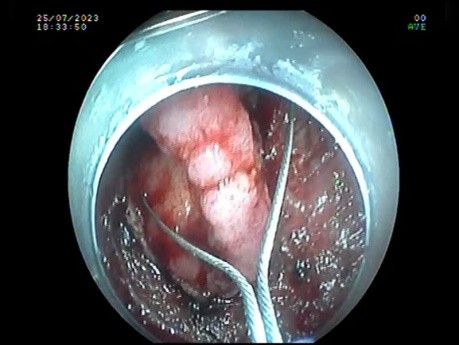

Resekcja zmiany o morfologii LST-G z centralną...

Film przedstawia resekcję zmiany z centralną depresją. Zmiana zwłokniała centralnie. Biosja przed kilkoma tygodniami wykonana przez innego operatora - obecnie stwarza trudność w resekcji "enblock"....